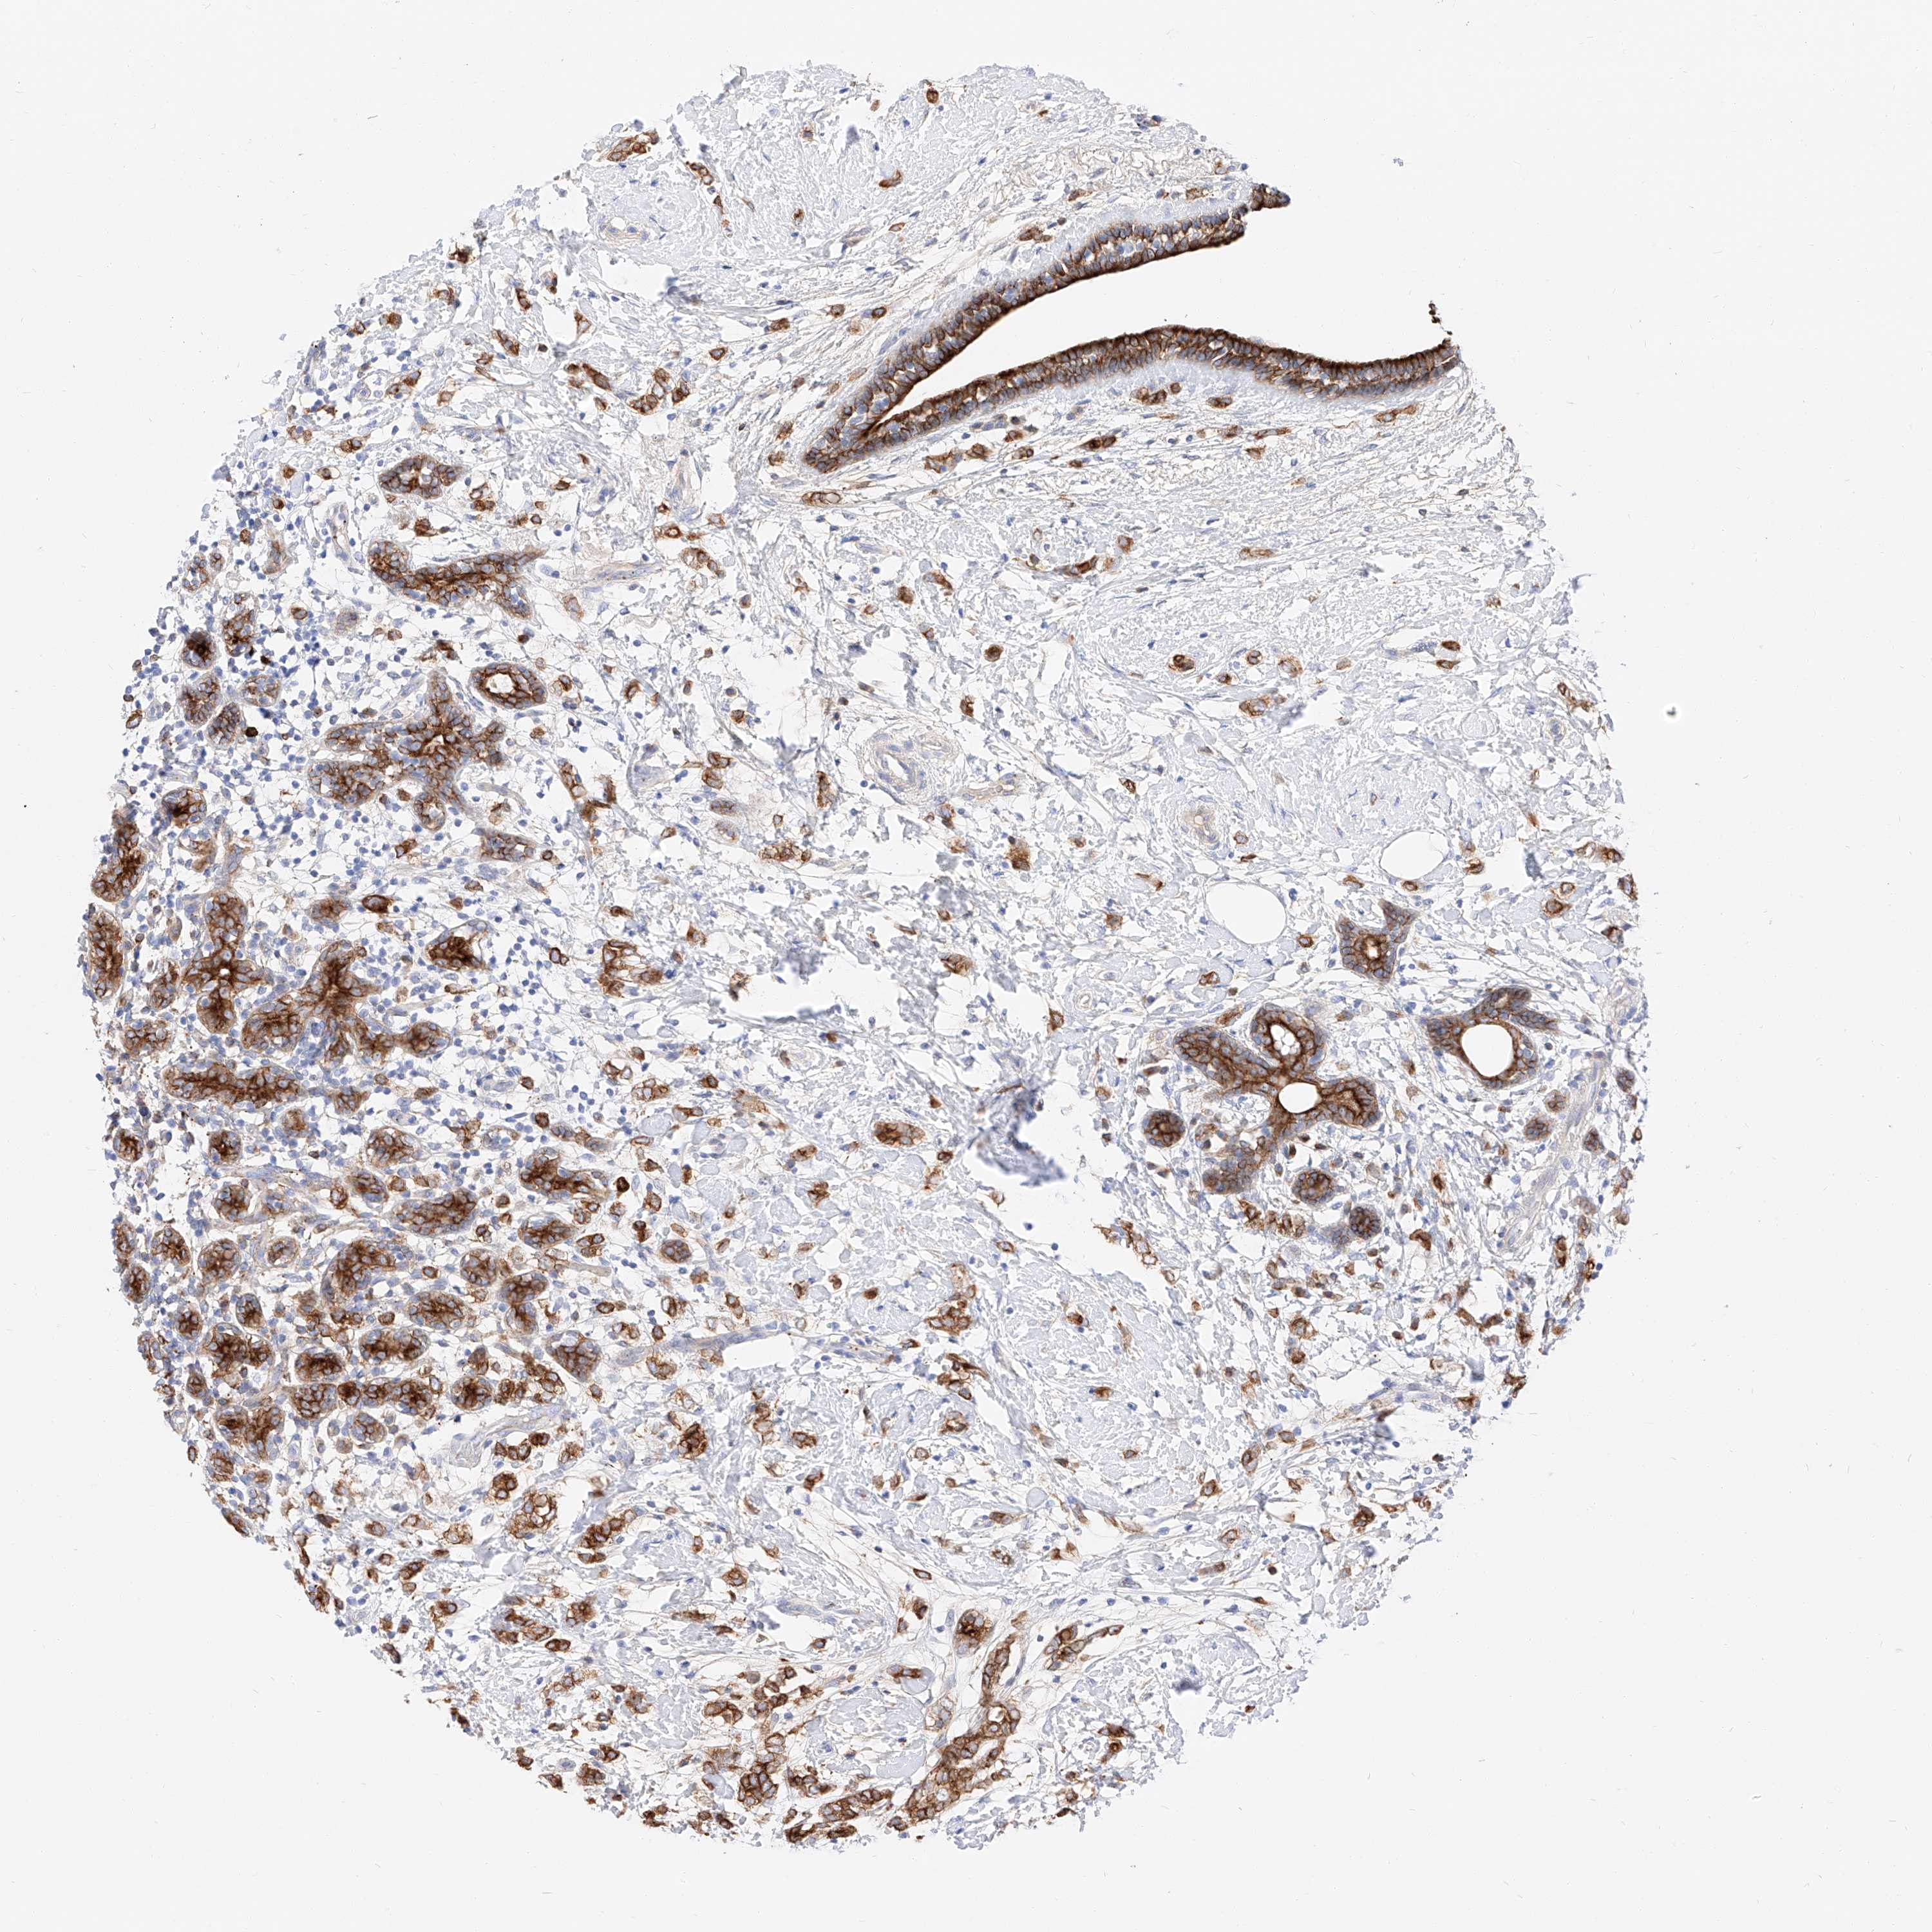

CANCER BREAST CANCER Show tissue menu

BRCA TCGA BRCA VALIDATION PROTEIN EXPRESSION